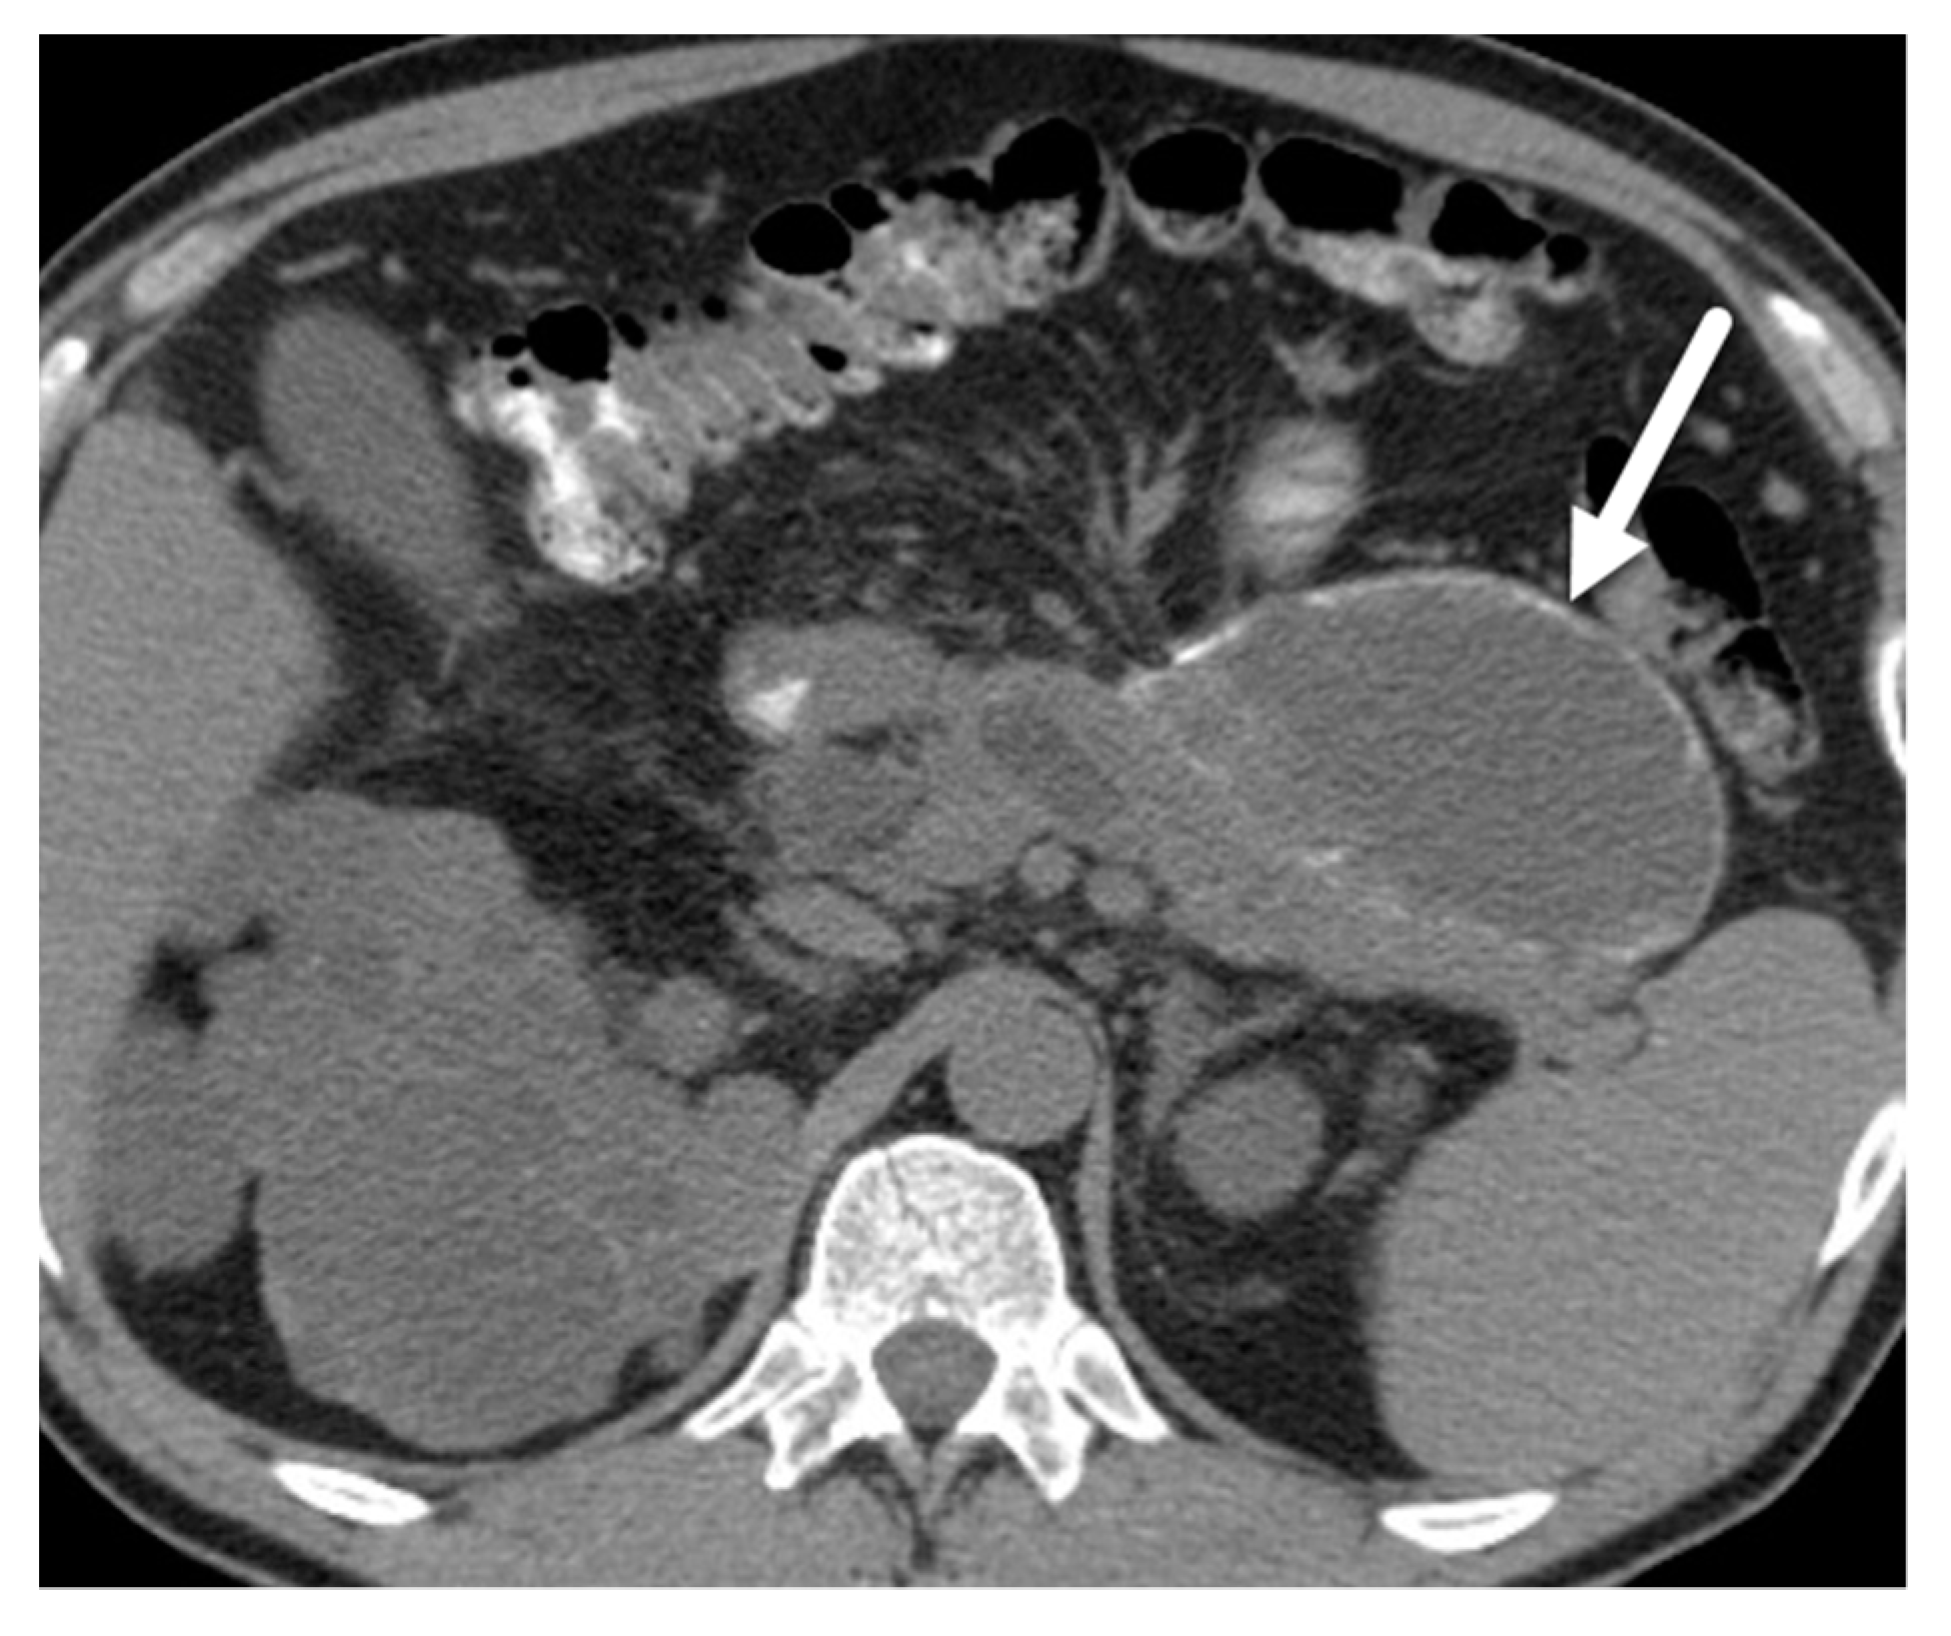

6.6. Cystic Neuroendocrine Tumor (Cystic-NET)